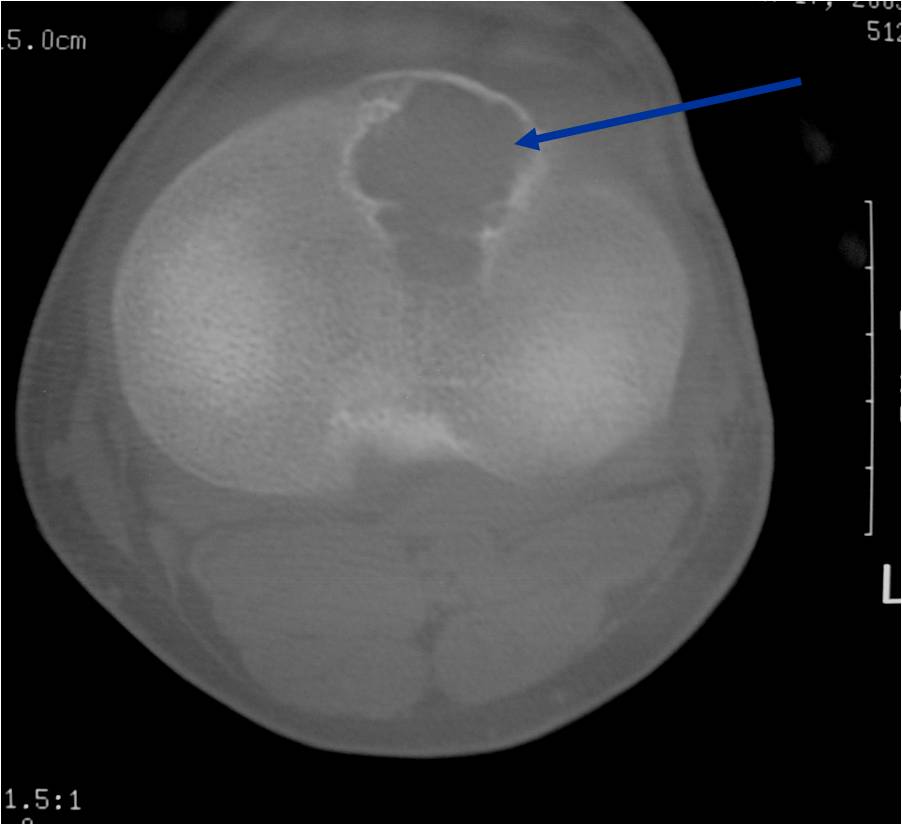

CT appearance:

- Most useful for detecting subtle mineralization not apparent on X-rays

- Useful for identifying intact periosteum around any expansile soft tissue component

- surrounding thin reactive shell of bone/mineralization (Egg Shell Rim of Calcification)

- helps place the tumor in a benign category

- helps evaluate:

- bony quality

- extent of bone and cortical destruction

- whether the subchondral plate of bone adjacent to the articular cartilage has been destroyed or is intact